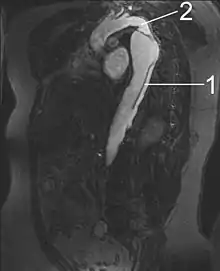

| Dissection of the descending part of the aorta (3), which starts from the left subclavian artery and extends to the abdominal aorta (4). The ascending aorta (1) and aortic arch (2) are not involved in this image. | |